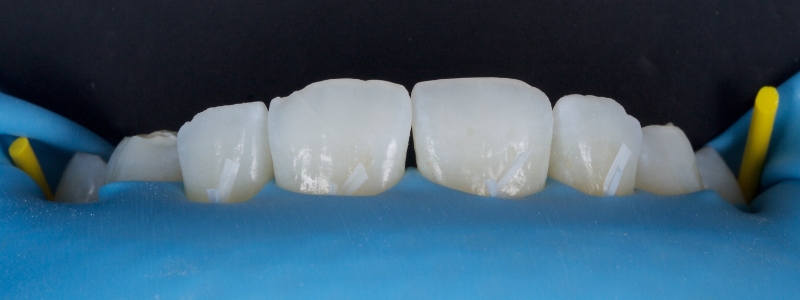

A diagnosis of altered passive eruption (APE) alongside tooth surface loss (TSL) secondary to parafunction was made for a referred female patient in her early 20s who complained of having“short, fat, baby teeth.” Due to her age, she was treated with a simple gingivectomy (after bone sounding), nightguard vital bleaching (NGVB), and additive edge bonding.

The worn incisal edges were restored with edge bonding, a new technique for restoring worn dentition. This should be regarded as a multiple Class IV restoration.